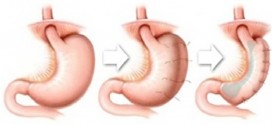

Es un trastorno del tubo que lleva el alimento de la boca al estómago (esófago), el cual afecta la capacidad del esófago para movilizar el alimento hacia este último. Un anillo muscular en el punto donde el esófago y el estómago se unen (esfínter esofágico inferior) normalmente se relaja durante la deglución. El esófago es un tubo muscular que conduce …